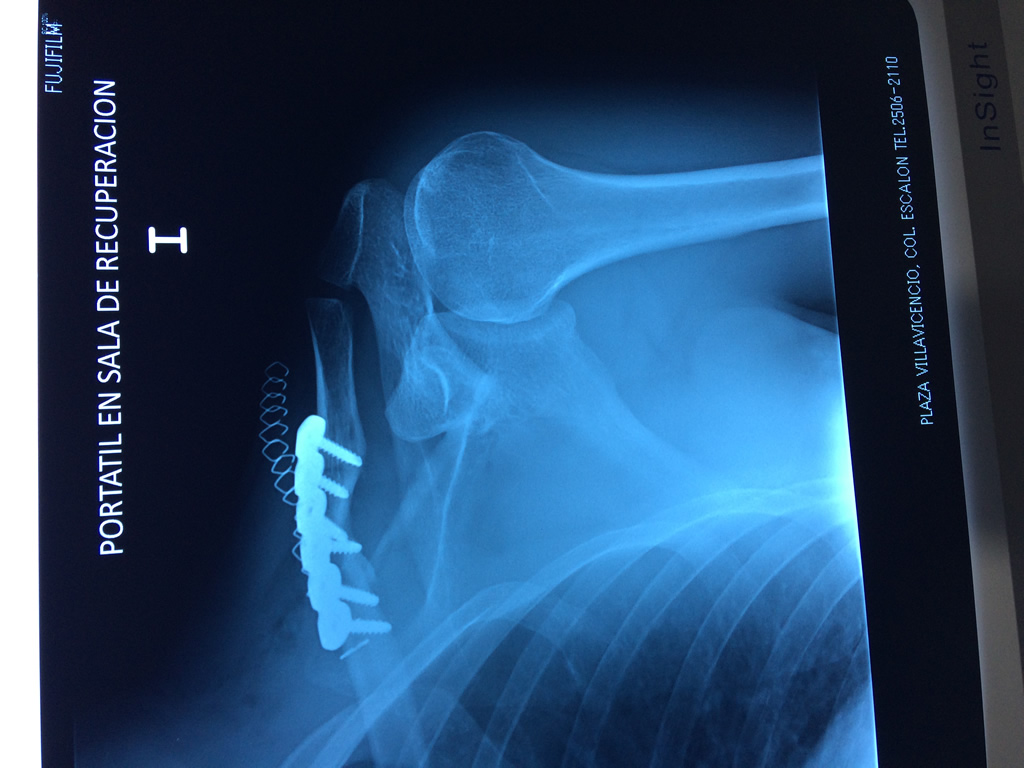

Cirugías de Codos - Clavícula